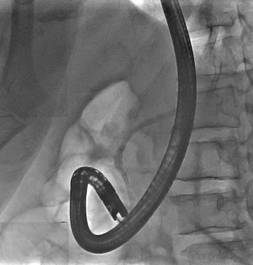

诊疗过程:患者高龄,一般情况差,手术风险高,患者及家属选择ERCP胆道支架植入及光动力治疗(不开刀、经自然腔道的微创手术,患者痛苦小)。ERCP术中因胆总管下段闭塞导丝不能进入胆总管,但是胰管插管成功,予以放置胰管支架(可改善胰管引流不畅,减轻胰管高压,改善消化功能);二期予以经皮经肝胆管穿刺(PTC)成功放置胆道支架(同样为微创,只需皮肤切开3mm的小口);待患者黄疸消退、全身情况改善后予以内镜下胆道肿瘤光动力消融术。术后多次复查腹部CT均提示胆总管下段肿瘤呈坏死的低密度灶,无复发征象。

经皮经肝胆道穿刺顺行疏通胆总管 |

胆管支架放置成功,造影剂顺利经支架流入肠道 |